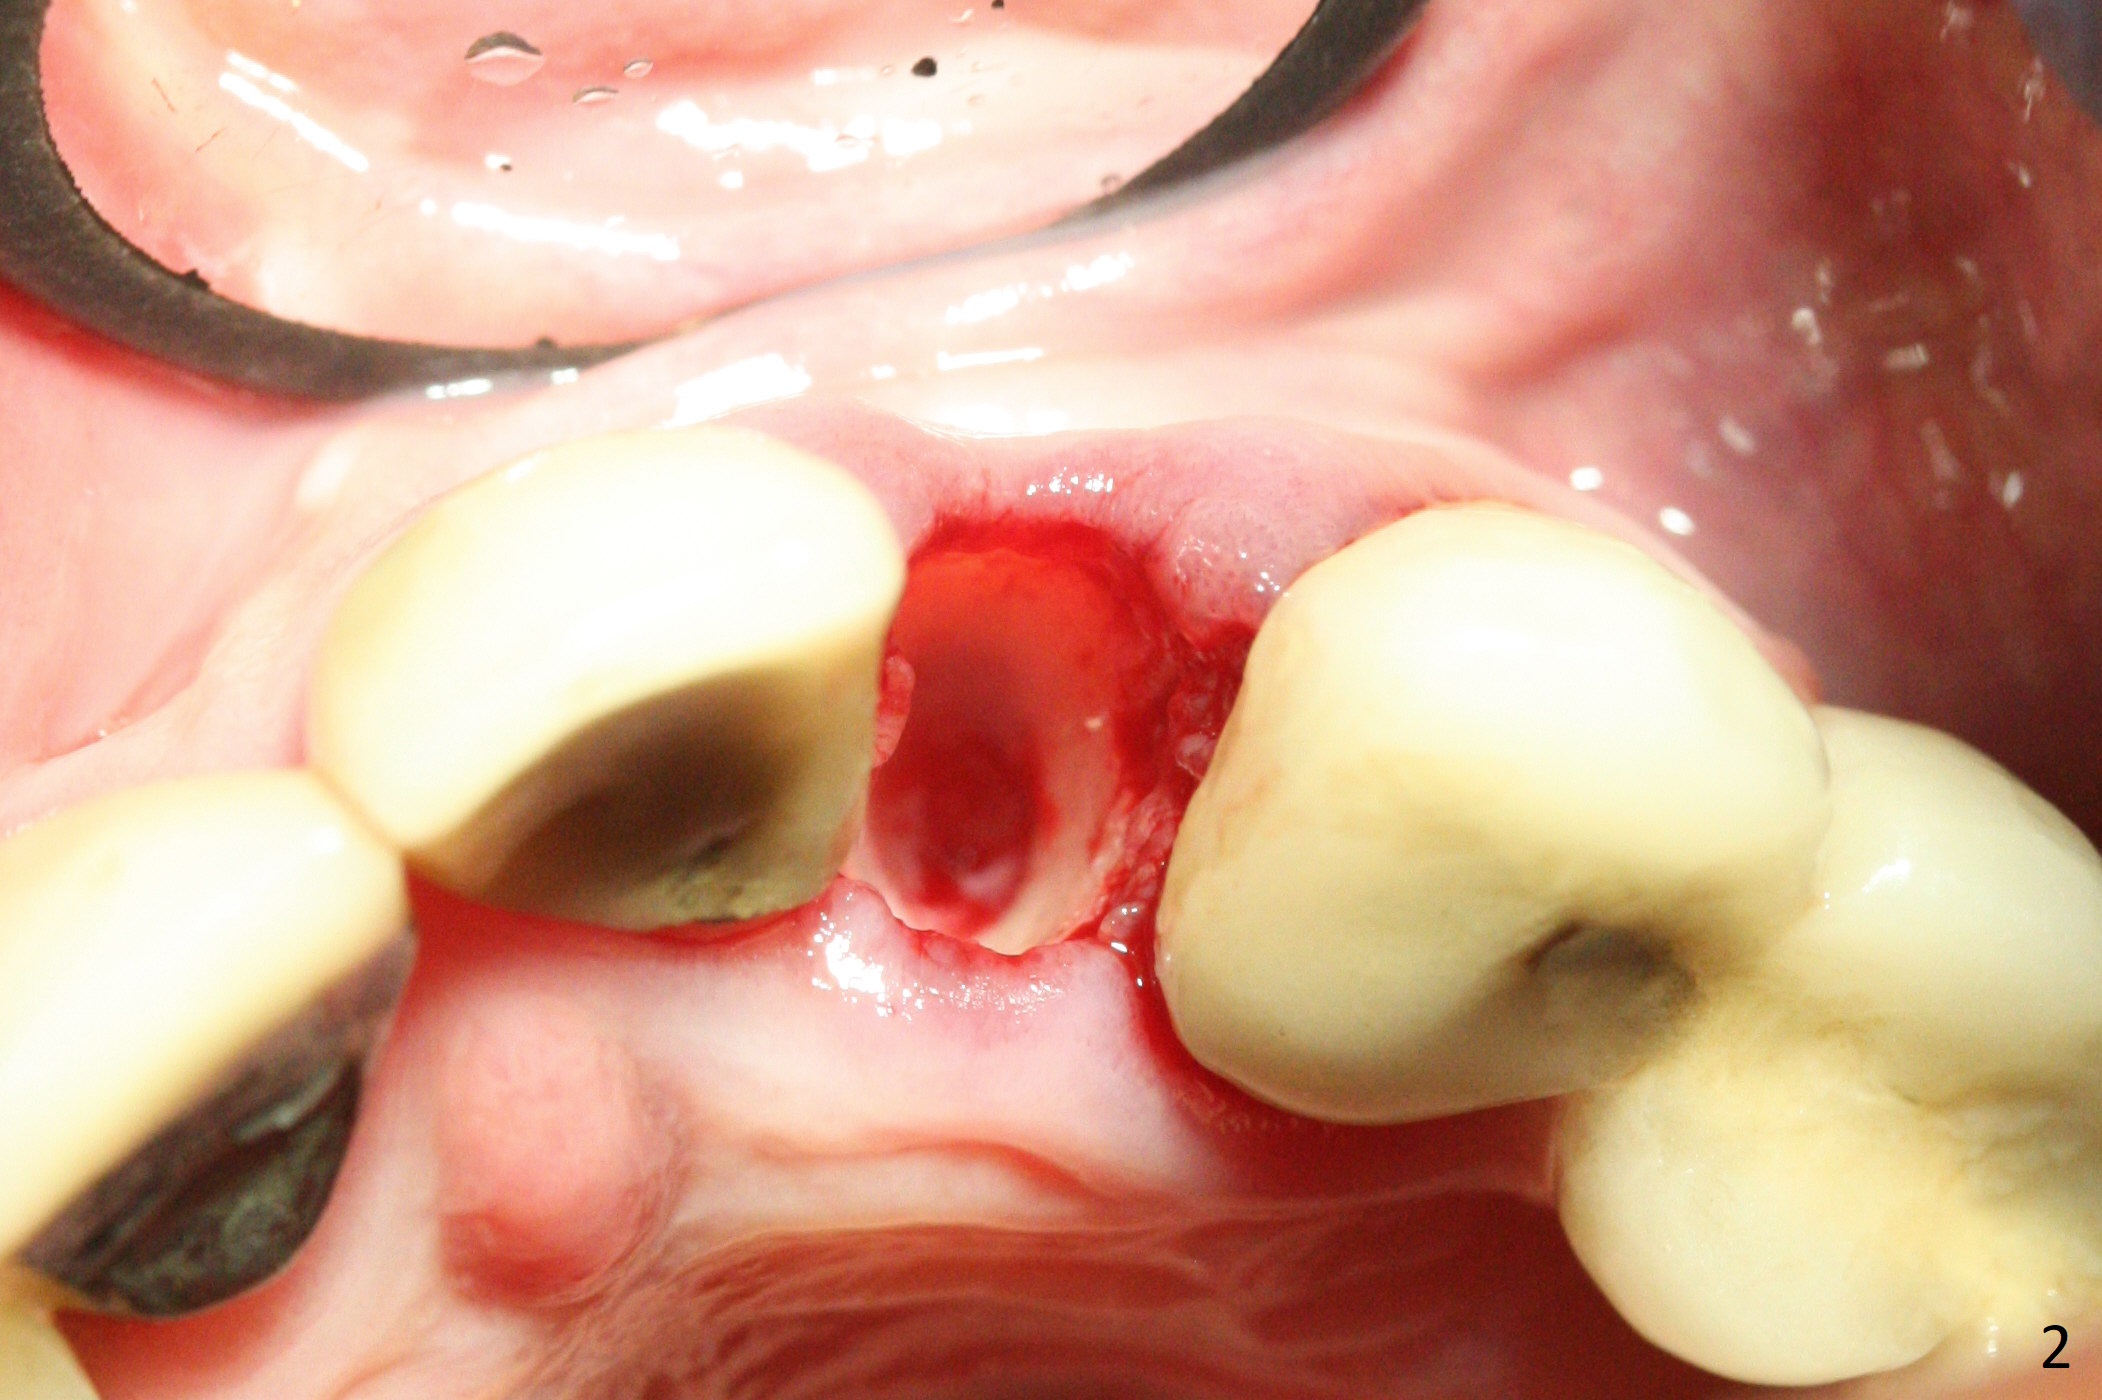

The tooth #10 fractures at the cervix, but is attached to the gingiva.  After extraction of the coronal portion of the tooth, the mesiodistal space palatally is found to be narrow (~4.7 mm, Fig.1).  It appears that a 1-piece implant is indicated because of the narrow mesiodistal space.  In fact the buccal plate of the socket is intact (Fig.2).  The initial osteotomy seems to be mesial (Fig.1) and is moved distal using Lindamann bur.  After sequential osteotomy, a 3x10 mm dummy implant is still mesial (Fig.4).  Following further distalization, a 3x14 mm implant is placed (Fig.5,6; <30 Ncm).  Vera Graft is placed in the remaining socket prior to provisional fabrication (Fig.6 *).  The socket outline disappears 7 months postop (Fig.7).  Panoramic X-ray is taken 1 year 3 month post cementation.